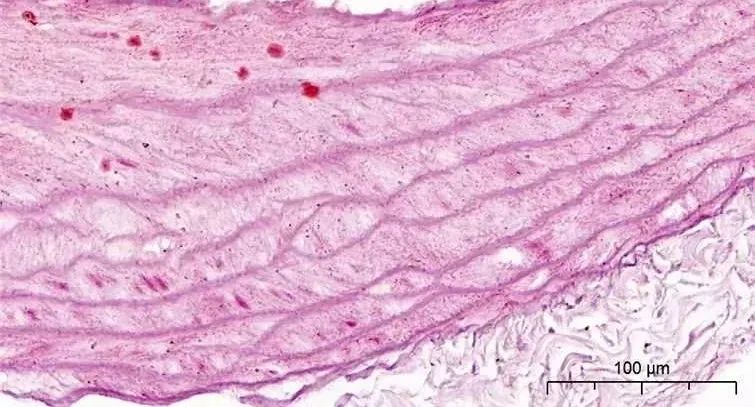

茜素红染色

茜素红(Alizarin Red S)是一种常用的染色方法,实质是一种蒽醌衍生物,常用来体外检测组织切片或者培养细胞的钙质变化。机体内的钙,一方面构成骨骼和牙齿,另一方面则可参与各种生理功能和代谢过程,影响各个器官组织的活动。茜素红的作用机制在于它能与碳酸钙或磷酸钙中的钙盐螯合形成橙红色复合物。

在干细胞分化为成骨细胞的过程中,细胞表面会沉积钙盐,形成钙结节。通过使用茜素红染色,可以染出这些钙结节,从而判断干细胞是否成功分化为成骨细胞。

茜素红染色实例